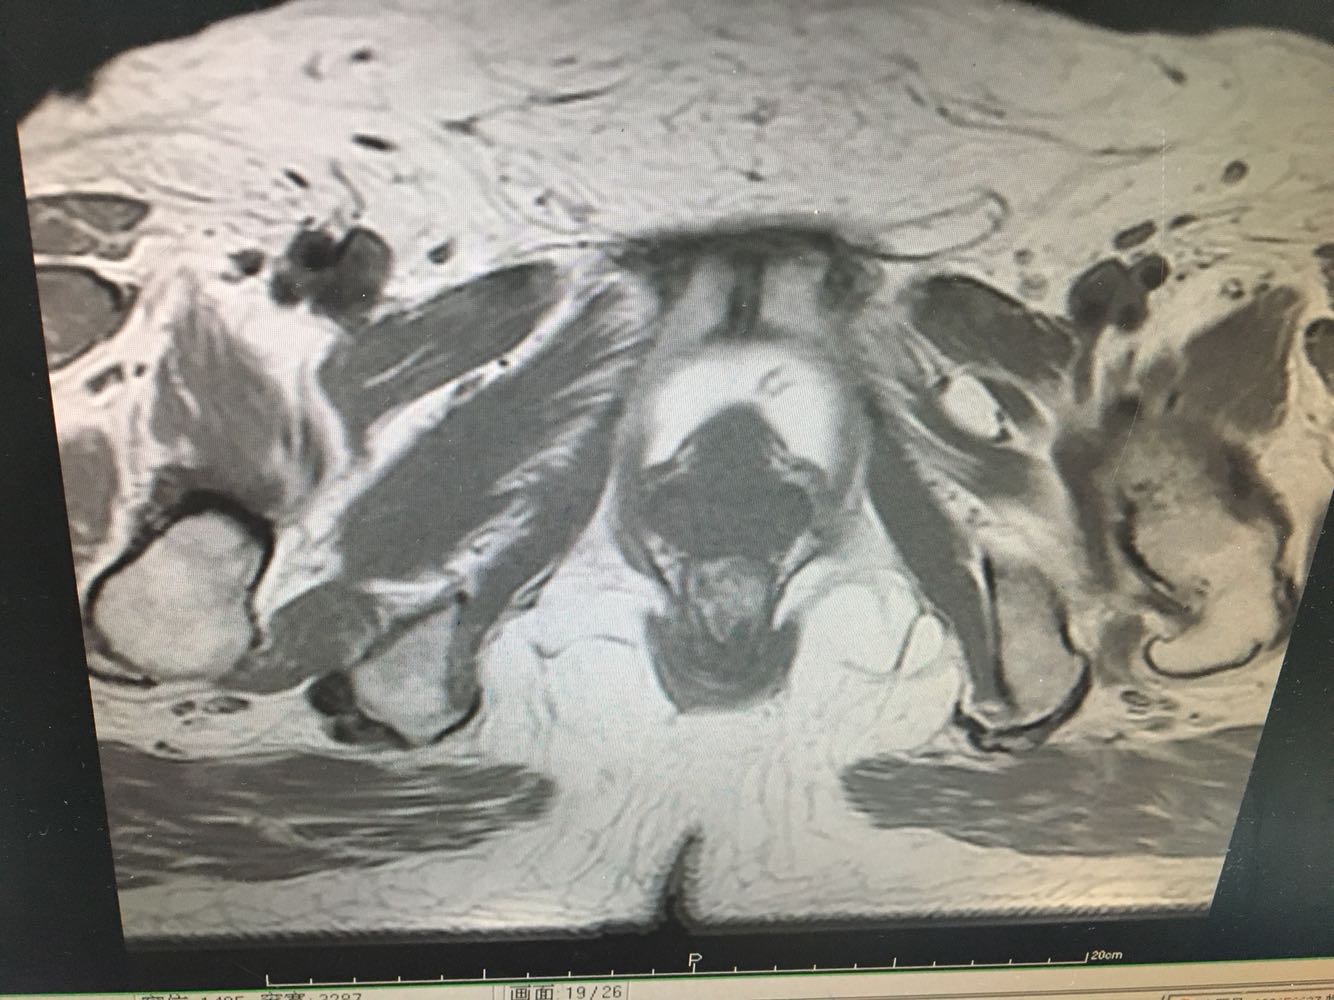

妇科检查:外阴:未见异常;阴道:畅,少量白色分泌物;宫颈:肥大,光滑;宫体:前位,如正常大小,无压痛,活动度好,双附件:未触及异常。        辅助检查:【妇科B超】现子宫肌层回声尚均匀,内膜厚9 mm,回声不均匀,双侧卵巢未显示,盆腔内未见明显异常血流信号,提示子宫内膜增厚不均。 行手术治疗。

诊断:  1、绝经后出血;2、子宫内膜增厚(性质待定) 诊疗方案:患者入院后完善各项检查,今全麻下行腹腔镜下宫腔镜子宫内膜活检+宫腔赘生物摘除+宫腔镜下刮宫 。切除赘生物3枚,分别取出送病理。宫腔镜下沿宫腔四壁搔刮,无明显组织刮出。手术顺利。术后给予抗炎治疗,观察阴道出血少,生命体征平稳,准予出院。